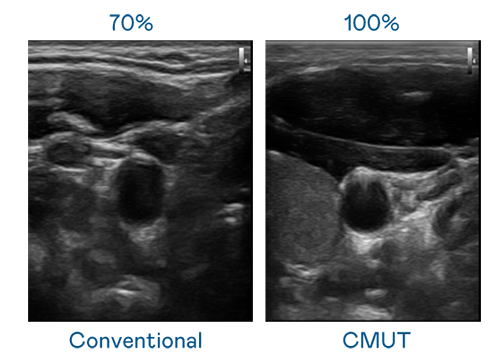

CMUT 技术是一种用电容式微机电元件来产生超音波讯号的技术。与传统 PZT 压电式技术相比,CMUT 频宽增加 30%,更宽频的超音波讯号让影像解析度大幅提升,是实现高影像品质医疗超音波扫描、促进精准医疗发展的关键技术。

大频宽带来超清晰影像

超音波影像的解析度高低,首先取决于探头能发出的讯号频宽。伟德国际1946 CMUT 可提供高清晰的超音波讯号,提供高频宽、高灵敏度、影像纹理细节更高的超音波影像,协助医护人员缩短影像判读时间及利用精准的医疗影像进行诊断。